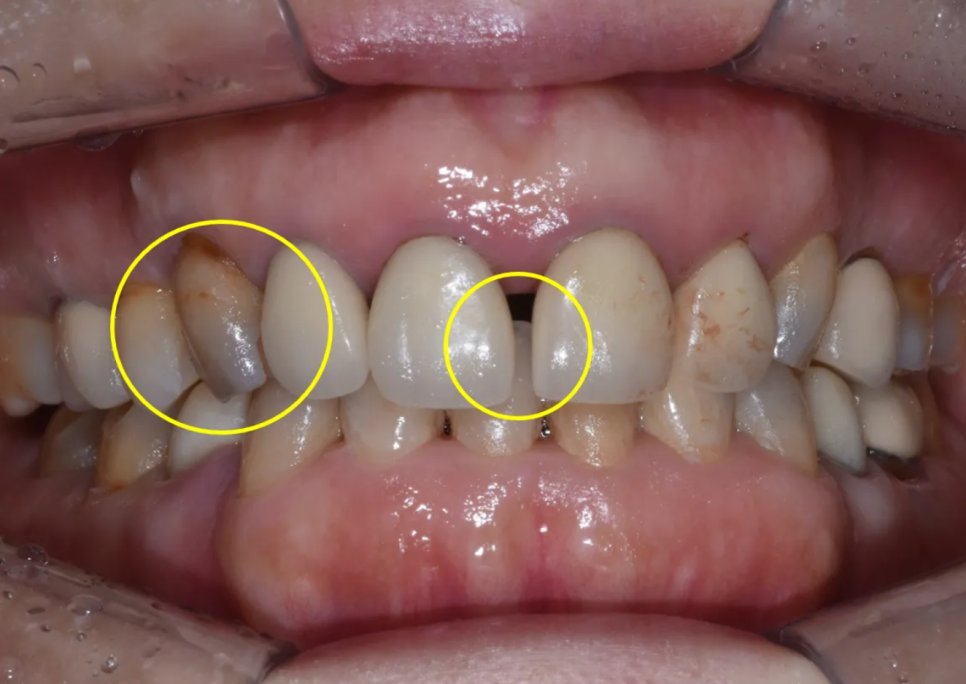

구내 검사 – 기존 크라운과 치아 상태의 문제점들

입 안을 자세히 살펴보니, 문제점이 한두 가지가 아니었습니다. 정리하면 다음과 같습니다.

| 기존 크라운 상태 | 오래된 도재-금속(PFM) 크라운의 마진 부적합, 변색, 치아 간 색상 부조화 |

| 앞니 사이 공간 | 가운데 두 앞니 사이, 그리고 왼쪽 앞니들 사이에 벌어진 공간 존재 |

| 오른쪽 송곳니 | 변색, 잇몸 쪽 마모(법랑질 닳음), 잇몸 퇴축 |

| 왼쪽 송곳니 | 절단면(끝부분)이 닳아 있는 상태 |

| 양쪽 송곳니 공통 | 치아 축이 안쪽으로 과도하게 기울어져 있음 |

| 블랙트라이앵글 | 오른쪽 앞니-작은앞니-송곳니 사이에 검은 삼각형 공간 존재 |

| 정중선 | 위아래 치아의 가운데 선이 맞지 않는 상태 |

한마디로, 심미적으로 개선해야 할 부분이 아주 많은 케이스였습니다. 일본의 치과에서 거절당하셨던 이유도, 기존 치아의 심한 손상 상태(포스트+코어)와 더불어, 이런 복합적인 문제들 때문이었을 것으로 추측됩니다.

앞니 사이 아주 큰 공간이 있고, 환자분 기준 우측 송곳니는 변색이 아주 심합니다

송곳니는 안쪽으로 많이 기울어져 있습니다

치아 사이 공간(블랙 트라이앵글)도 심한 편입니다

치아 사이 공간이 보이고, 송곳니가 많이 닳아 있습니다